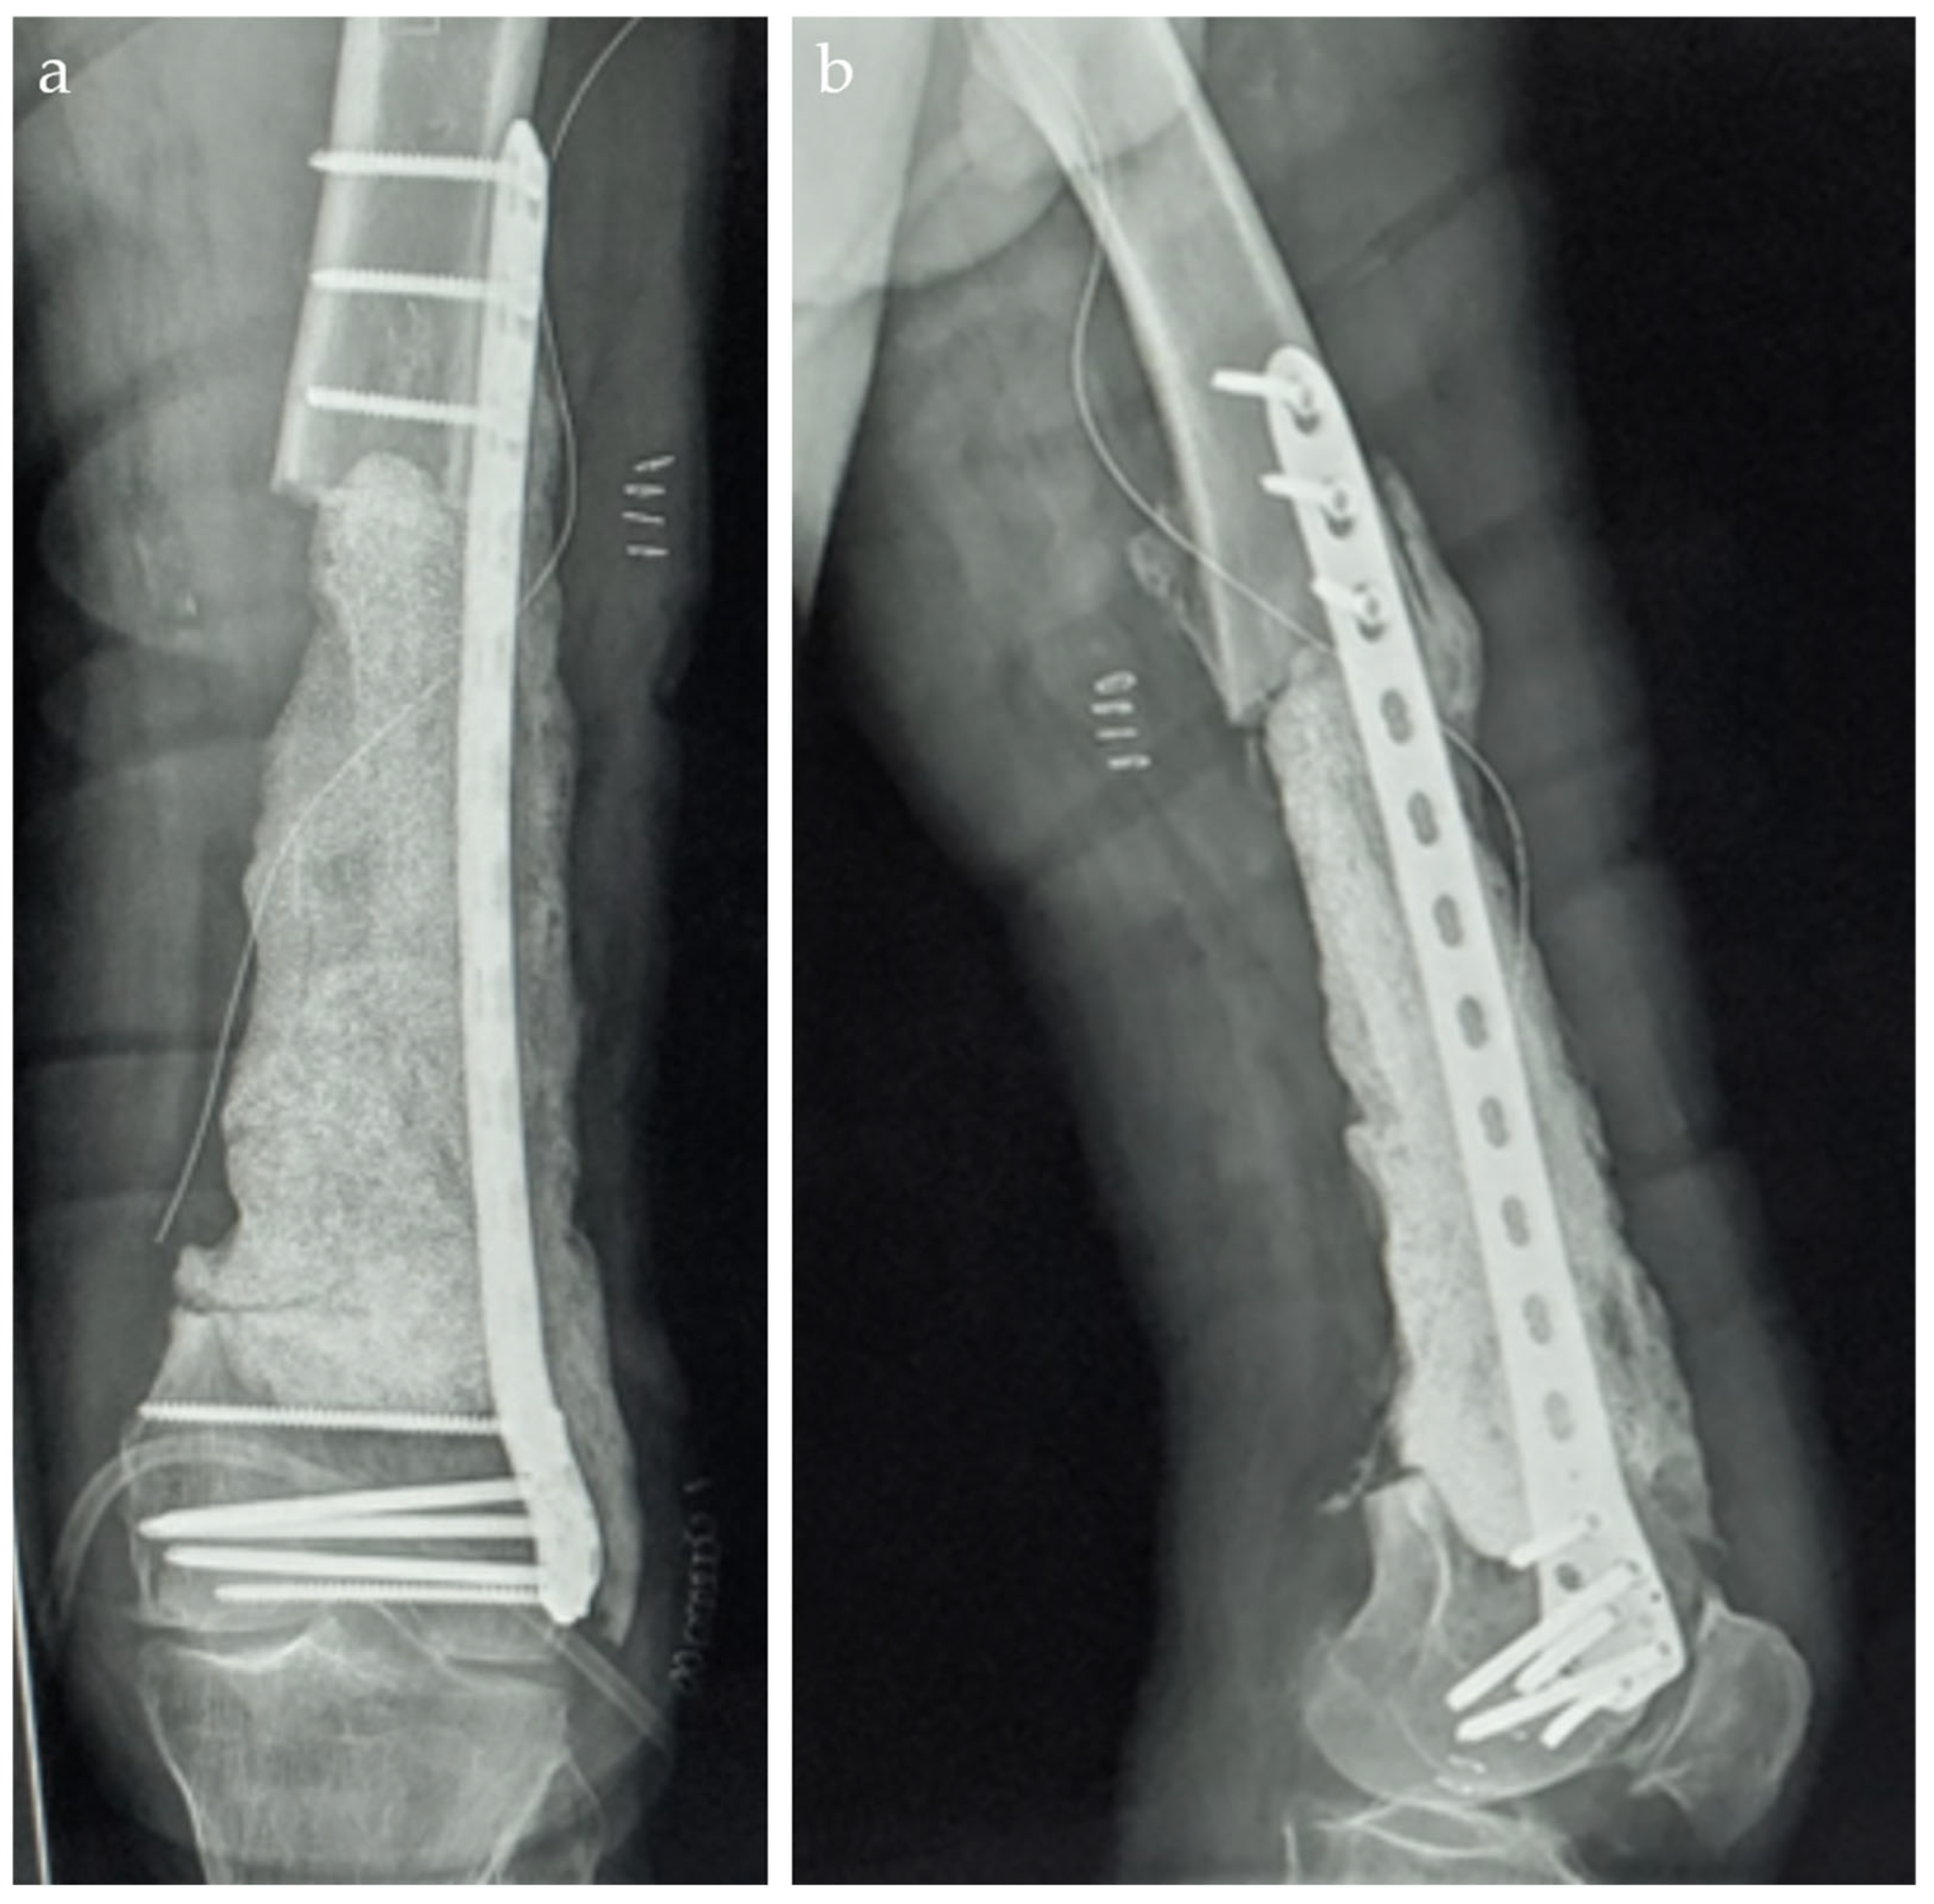

2. Case Report